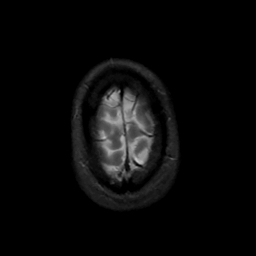

MR Study #8, March 31, 1991 -- Slice #46

[Home][Help][Clinical][Tour 1][Tour 2] Slice 46